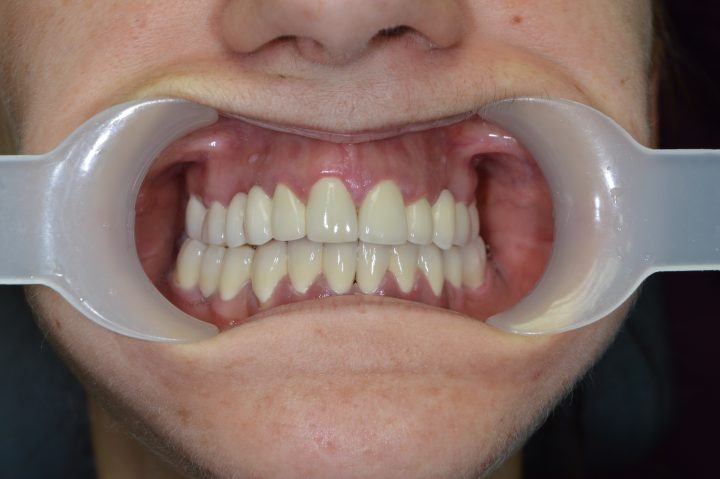

Ibrahim ist einen von den französischen Patienten, wer früher sowohl oben, als auch unten herausnehmbare Zahnersatz hatte. Die Prothese hatte große Gaumenplatte, und deswegen konnte er die obere nicht tragen.

Er hatte ständig Brechreiz, und hat immer gewürgt, daneben war die Stabilität auch problematisch.

Die Prothesen haben sich ohne Klebstoff bewegt, und er hat sich aufgeregt, wenn er gesprochen hat. Er hatte davon Angst, dass die Prothese einmal ausfällt. Deswegen hat er die Klinik besucht.

Er hat oben und unten festsitzende Prothese auf Implantaten bekommen, womit er restlos zufrieden war. Diese Prothesen bewegen sich nicht weder beim Kauen, noch beim Sprechen.

Dank der Prothese, die keine Gaumenplatte hat, kann er sorglos den Zahnersatz tragen.